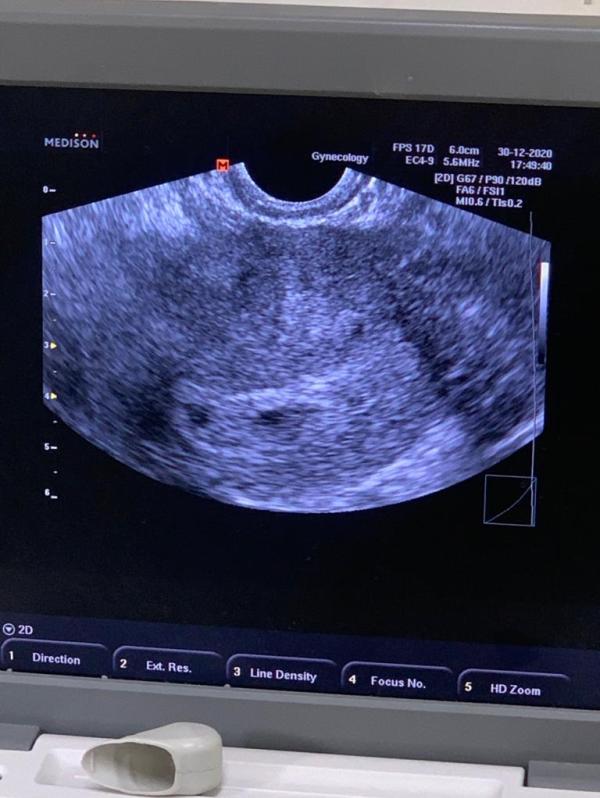

Девочки, врач отправила мне вчерашние фотки.. У кого были двойни, так ли было на 5-6 неделях? Меня смущает их размеры-один побольше, другой поменьше, третьего и не видно..

Вчера порылась в нете, в ютубе, там говориться, что иногда такое бывает что вмдем 2 плодных яйца, но в одном эмбрион.. Со временем второй исчезает.. Я это к чему, у меня таксикоза вообще нет, в роду ни у кого двойняшек нет, возраст не большой, живот вроде не сильно растет, может ли быть ошибка? Может было у кого то такое🙈

Она сказала похоже на тройняшек, но 2 точно есть

@katrin757 аа, поняла вас.. Просто там где побольше, сказала 6 недель и серцебиение уже заметно